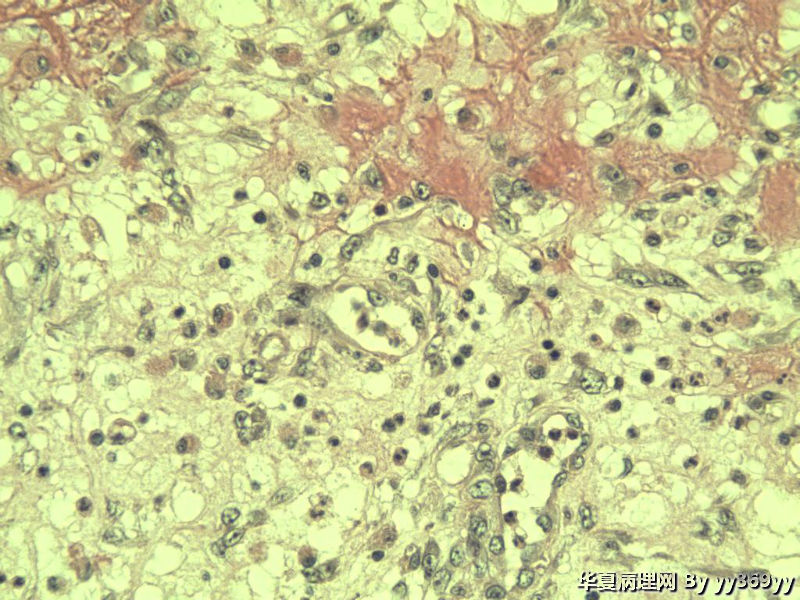

男 30岁 小肠一段,肠管严重粘连可见一体积为 2.5 × 2 × 1.5 cm3的肿块,切面灰白,实性,质中

小肠肿瘤图1

从最后这几张高倍镜图看,淋巴样细胞弥漫性增生,很可能是淋巴瘤。

恶性肿瘤   淋巴瘤 脂肪肉瘤  低分化腺癌 做IHC

考虑炎性肌纤维母细胞瘤、炎性纤维性息肉、胃肠间质瘤,不考虑淋巴瘤

考虑炎性肌纤维母细胞瘤

只是倒数那几张是取自淋巴结吗,还是所有的? 考虑恶性GIST,做IHC